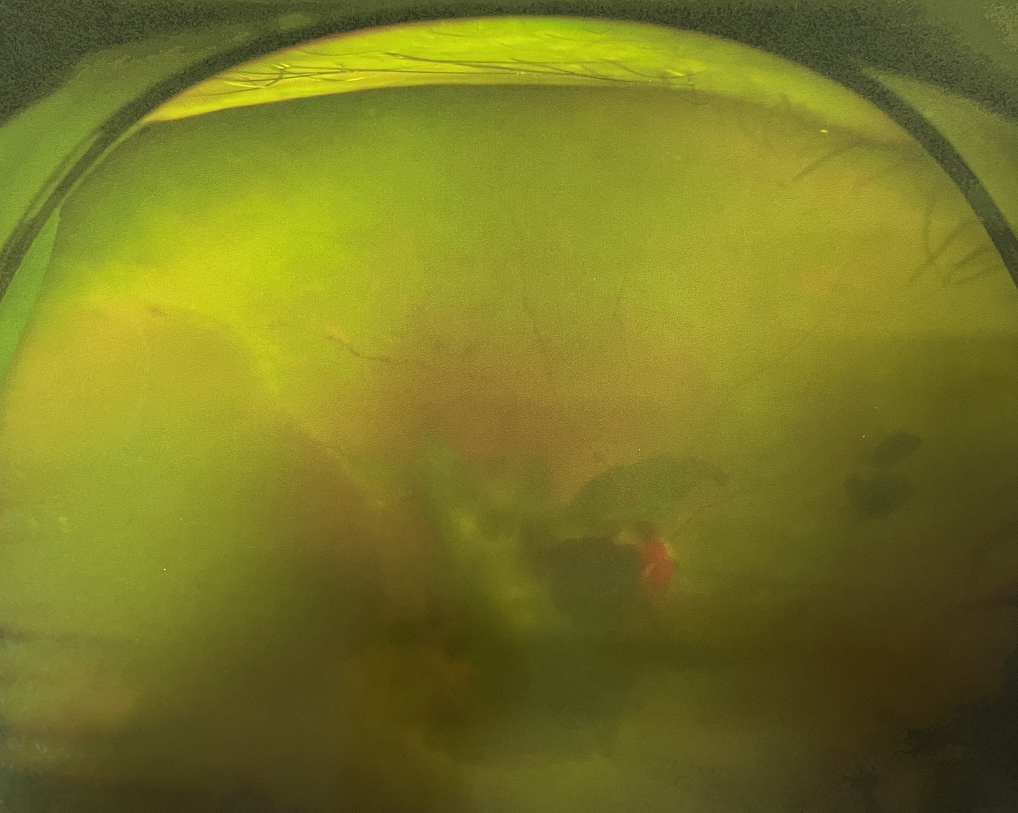

眼底出血多指玻璃體內(nèi),眼睛更深處的視網(wǎng)膜出血。通常情況下,肉眼難以發(fā)現(xiàn)眼底出血,而且發(fā)病初期眼睛也無明顯癥狀,只有借助專業(yè)的眼底檢查儀器才能觀察到異樣。那么眼底出血嚴重嗎?

誘發(fā)眼底出血的原因眾多,常見的有全身性血管病和血液病、視網(wǎng)膜血管異常、機械性阻塞、炎癥性疾病或免疫復合物侵犯血管壁等。

眼底出血嚴重嗎?其中,“三高”患者、高度近視患者和滲出性或濕性老年黃斑變性患者是眼底出血的高發(fā)人群。

醫(yī)生提醒,一旦眼睛出現(xiàn)視力下降、視物變形、視野缺損或眼前有黑影等視覺“異常”的情況,應及時到醫(yī)院進行眼底檢查,及早發(fā)現(xiàn),及早治療,以免貽誤病情。

眼底出血嚴重嗎?對于已出現(xiàn)黃斑水腫、視網(wǎng)膜新生血管的患者,根據(jù)眼底血管造影、oct等檢查結果,給予玻璃體腔注射抗VEGF藥物及激光治療,可以減輕黃斑水腫,使視網(wǎng)膜新生血管消退,以免進一步發(fā)生玻璃體出血、視網(wǎng)膜脫離等嚴重并發(fā)癥的出現(xiàn)。對于玻璃體出血者,傳統(tǒng)認為玻璃體出血3-6個月不吸收再進行手術干預,但近年來因為顯微手術設備及玻璃體切割技術已非常成熟,故對于1個月不吸收的玻璃體出血者就可以考慮手術,即手術時機應該具體情況具體分析,因人而異。